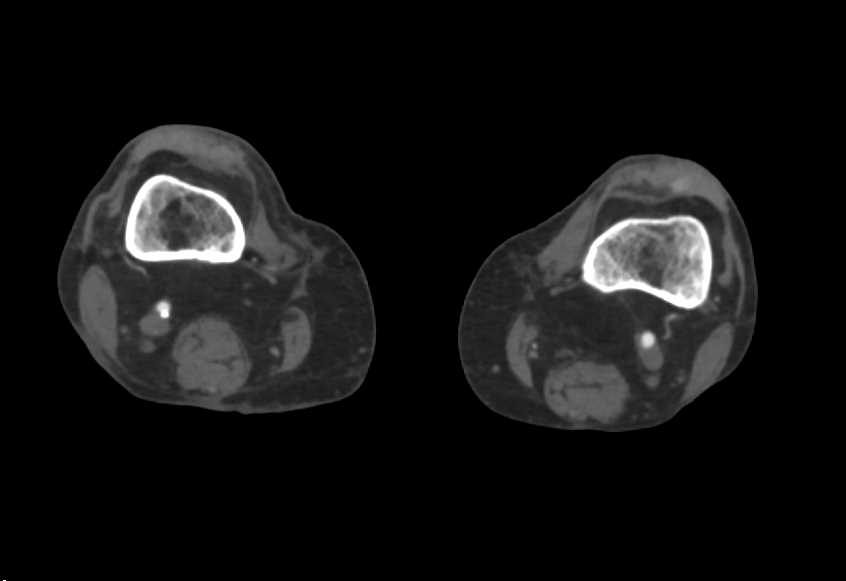

Multiple Aortic Aneurysms